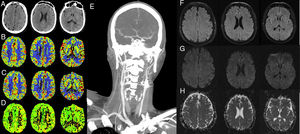

Our patient was a 41-year-old man with a history of locally relapsing squamous cell carcinoma of the nasopharynx; he had previously been treated with surgery, chemotherapy, and radiotherapy, and was admitted electively to our centre for surgical reintervention. Three months before surgery, the patient underwent an angiography-based balloon test occlusion of the carotid artery (200mL of non-ionic iodinated contrast agent were administered), which confirmed that there was sufficient flow compensation by the circle of Willis and the absence of neurological symptoms. The day before the procedure he underwent embolisation of the left internal carotid artery in 2 locations: proximally, beyond the carotid bifurcation, and distally, proximal to the ophthalmic artery (Fig. 1). For the angiography, we used 310mL of non-ionic iodinated contrast. The procedure was uneventful and the patient remained asymptomatic at all times. Renal function was preserved before and after the procedure (glomerular filtration rate >90mL/min) and his arterial blood pressure remained within normal ranges. Six hours after embolisation, the patient presented neurological signs of predominantly motor aphasia, right homonymous hemianopsia, and right facial paralysis. A blood analysis revealed no alterations and the electrocardiography showed sinus rhythm. The baseline sequence of a head CT scan using an iodinated contrast agent (50mL) revealed attenuation of sulci, suggestive of oedema, and cortical contrast uptake in the left hemisphere (Fig. 2A). CT angiography confirmed occlusion of the left internal carotid artery with excellent compensation of intracranial circulation, with perfusion sequences showing no alterations (Fig. 2B-E). In the acute phase, we started antiepileptic treatment with levetiracetam at 1000mg/12h and dexamethasone at 6mg/4h. An MRI scan performed at 24hours showed signal alterations on the FLAIR and DWI sequences in the left parietal and frontal cortex, with no restriction on the ADC map; these findings are compatible with vasogenic oedema. An electroencephalogram revealed slowing of the background rhythm in the left hemisphere. The patient improved clinically, with symptoms resolving 24hours later.

(A-E) Computed tomography: A) baseline axial CT slice showing sulcal effacement and cortical contrast uptake in the left hemisphere; B-D) CBV, CBF, and TTP maps, respectively, showing no alterations in brain perfusion, and E) coronal CT angiography slice confirming occlusion of the internal carotid artery after bifurcation, with excellent intracranial compensation. F-H) Magnetic resonance imaging: F) axial FLAIR slice; G-H) axial DWI and ADC sequences, respectively. Signal alteration is observed on the FLAIR and DWI sequences at left parietal and frontal cortex level, with no restriction on the ADC map, which is compatible with vasogenic oedema.